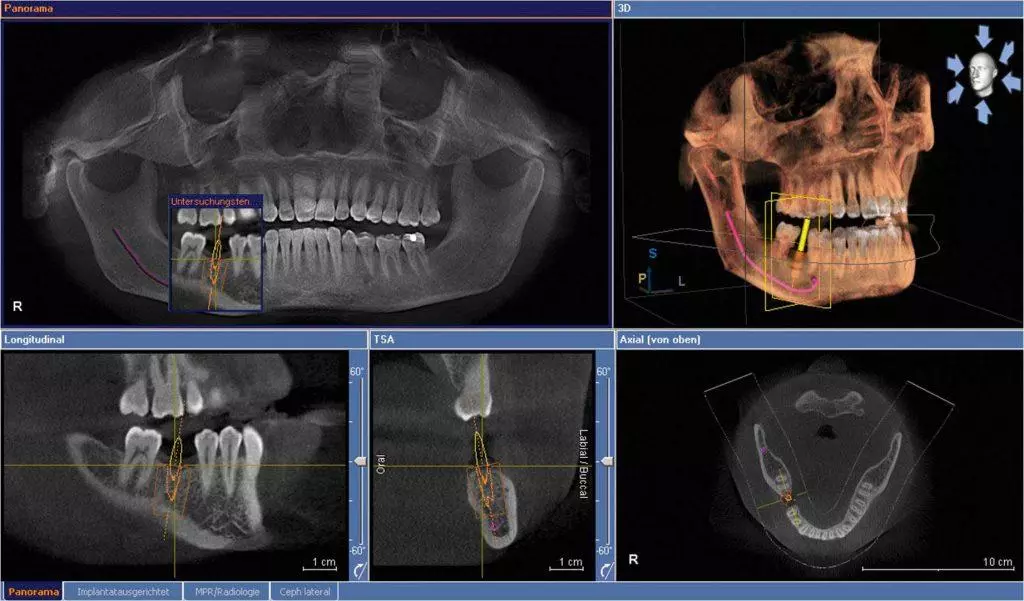

CT是一种通过多次X射线照片来生成三维影像的技术。它能够提供更为详细和准确的图像,显示牙齿和颌骨的各个方面,包括软组织和骨质。CT的使用范围更广,可以用于检查种植牙、口腔颌面部肿瘤、牙齿受伤等情况。

CBCT